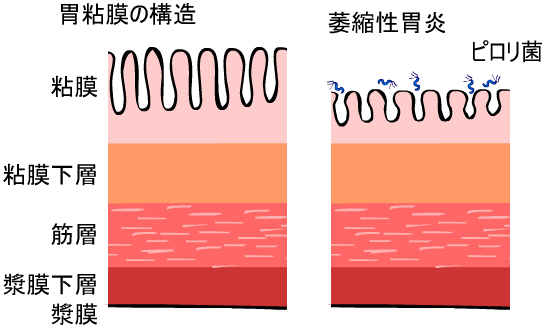

| ˆف’×ل‡(ƒsƒچƒٹ‹غٹ´گُ‚ة‚و‚é‚à‚ج) | |

| ˆف’×ل‡پAڈ\“ٌژw’°’×ل‡‚جŒ´ˆِ‚ج‘½‚‚ح ƒwƒٹƒRƒoƒNƒ^پ[ƒsƒچƒٹ‹غٹ´گُ‚ة‚و‚é‚à‚ج‚إ‚·پB ‚ـ‚½پAƒsƒچƒٹ‹غ‚جژ‘±ٹ´گُ‚حˆفٹà‚جŒ´ˆِ‚ة‚à‚ب‚è‚ـ‚·پB “–‰@‚إ‚حگد‹ة“I‚بڈœ‹غژ،—أ‚ً‚¨‚·‚·‚ك‚µ‚ؤ‚¢‚ـ‚·پB ƒsƒچƒٹ‹غ‚ج‰ًگà‚ح‚±‚؟‚ç •گ“c–ٍ•iچH‹ئ‡ٹ‚جHP‚ض‚جƒٹƒ“ƒN پ¦ƒsƒچƒٹ‹غ‚جژتگ^‚ح•گ“c–ٍ•iچH‹ئ‡ٹ‚©‚ç’¸‚«‚ـ‚µ‚½پB |